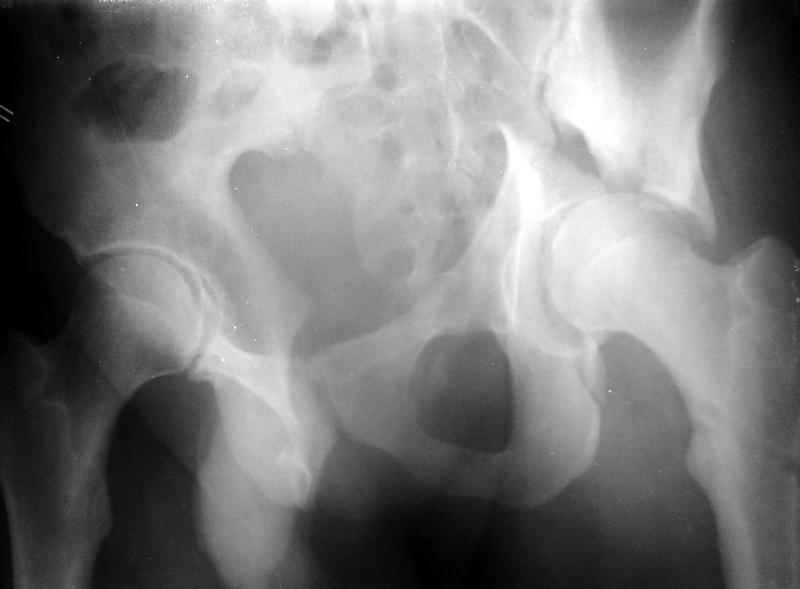

Сегодня на приеме был пациент, чьи начальный снимок напомнил обсуждаемый сейчас (см. выше). Снимки в других проекциях, показывающие истинный характер повреждения, ниже. Это inlet проекция (вход в таз) и запирательная проекция Judet.

1

2

Травма 17 ноября 2002 г., поступил к нам 1 декабря, оперирован 8-го - открытая репозиция, остеосинтез пластинками и винтами. Учитывая повреждение переднего полукольца справа, и крестца и крестцово-подвздошного сочленения слева, наложили аппарат на 2 месяца.

Для экономии места привожу интра- и послеоперационный обзорный снимок, без дополнительных проекций.